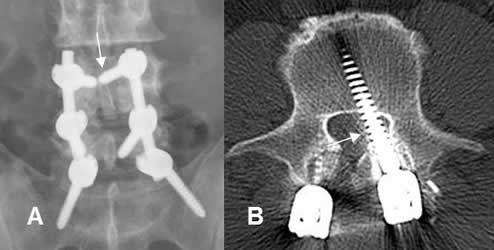

Fig 112. Mala posición de tornillos.

A: Rx AP. Tornillo superior muy medializado y que cruza la línea media.

B: TAC axial. Tornillo izquierdo mal ubicado. Ocupa la región paramediana izquierda del canal y puede lesionar la raíz nerviosa.